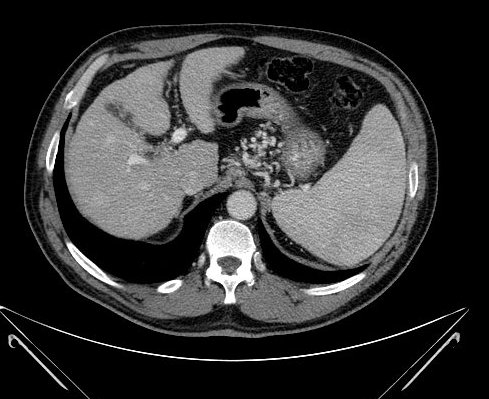

Very variable appearence forms can be observed by US and CT examinations from the early cyst in active phase to the cyst of the died parasite with a calcified wall (although the calcium appearing in the wall of the cyst does not mean that the parasite has unambiguously consumed) in case of an E. granulosus infection (Figure 15).

Figure 15: Echinococcus cyst in the liver, contrast enhanced CT

On the other hand, the liver parenchyma affected by E. multilocularis appears as areas with irregular contour and mixed echogenecity (US) or density (CT) including a hypoechoic (US) or hypodens (CT, this is already the necrotic area) necrotic center (multilocular cyst with inner matrix).